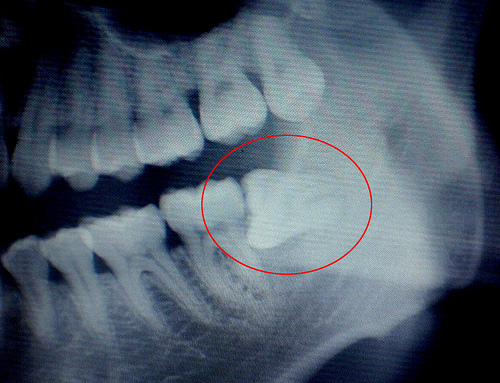

6、阻生齿:这种类型的智齿,通常埋在齿槽骨的里面,当你感觉到痛时,就要拔掉它。

其次,如果智齿长歪了,它和相邻的牙齿之间就会出现一个夹角,容易导致食物嵌塞,时间久了,智齿和相邻的牙齿都容易出现蛀牙甚至是牙髓炎。

2、侵犯邻牙:如果生长空间不足,智齿会使劲儿顶住相邻的牙齿继续生长,可能导致两颗牙齿都保不住。